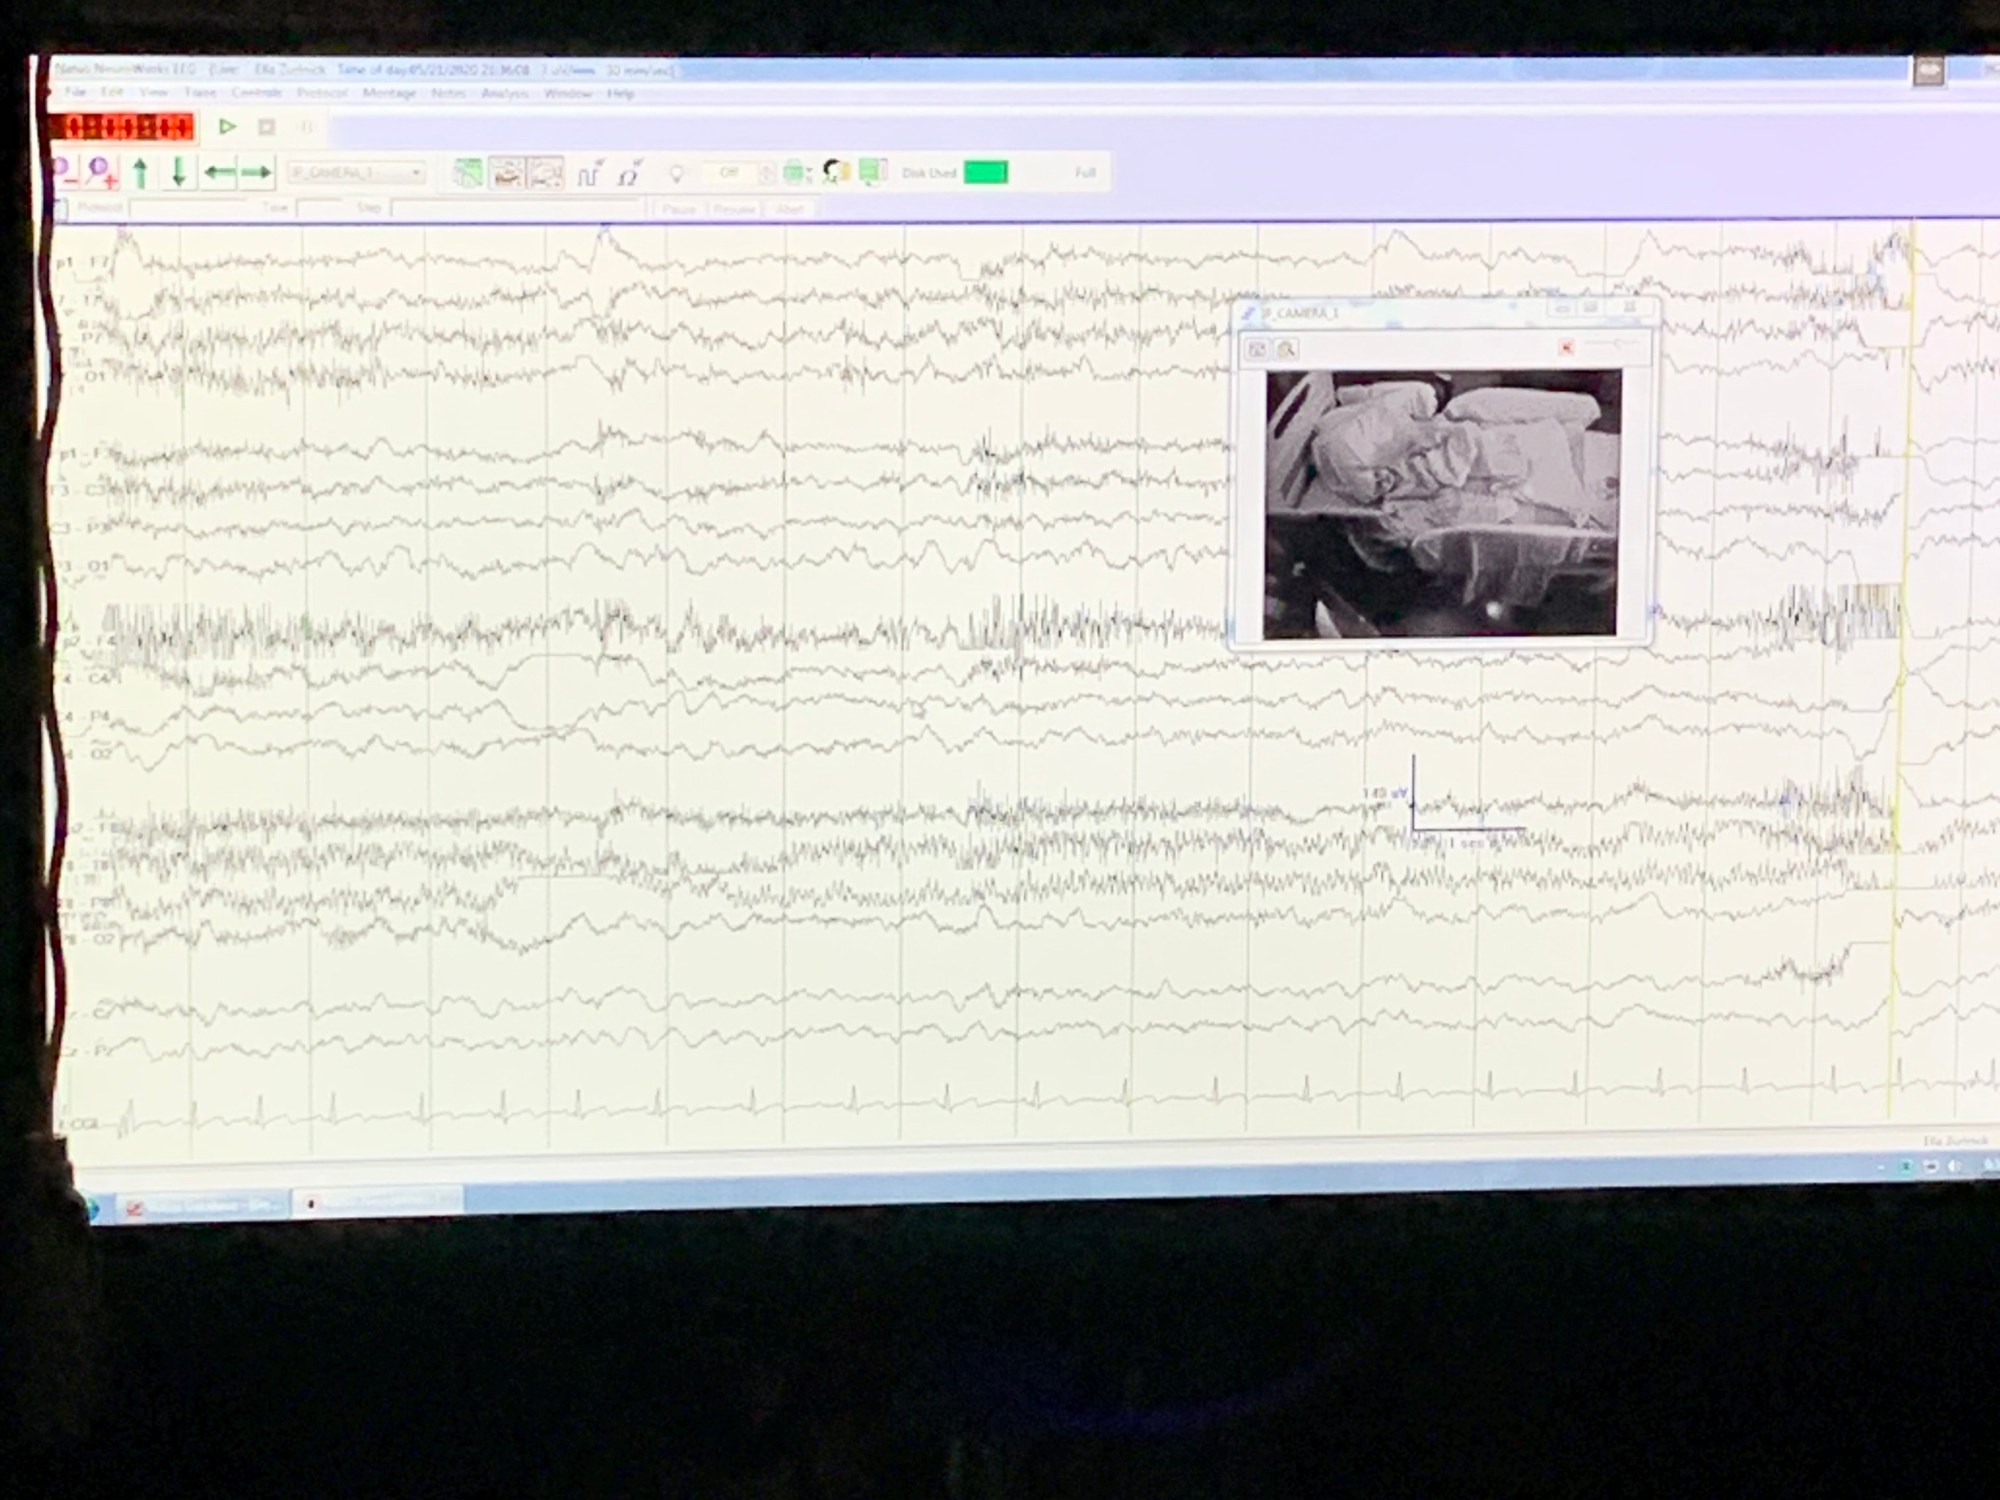

Finally Ella gave in and went to sleep. She was snoozing for about an hour and woke up in a much better mood, thankfully. Right after nap time the NP who works with the neurologist came in to discuss what they had been observing on the EEG thus far. She explained that they are seeing spikes in the back part of her brain while she is both awake and asleep. I asked if that was causing the seizures, and she said they could definitely be contributing to the episodes she is having. We weren’t surprised when they recommended another twenty four hours on the machine for monitoring. She emphasized the importance of getting as much data as possible. I would agree, the more the better.

About an hour after she came in, Steve got a call from Ella’s doctor at Columbia. She told Steve the same thing I was told, only she painted a mental picture of what is happening. She said the spikes are like striking a match and not having it light. That keeps happening over and over again. Finally when it lights, Ella has a seizure like she did the day we brought her in. It totally made sense.